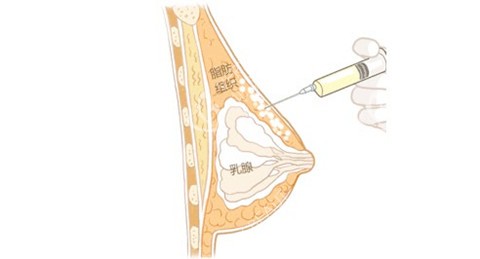

抽脂完成后,医生对抽取的脂肪进行了处理,将健康、有活力的脂肪筛选出来,准备注入乳房。接下来就是脂肪注射环节,医生小心翼翼地将处理好的脂肪一点一点注入乳房,调整乳房的形状和大小。手术持续了几个小时,结束后我被送回病房休息。

一般来说,脂肪的吸收率在30% - 70%左右,这受到多种因素的影响,比如个人体质、脂肪质量、手术操作等。我的体质可能对脂肪的吸收比较快,再加上手术过程中部分脂肪可能没有得到良好的血供,导致存活的脂肪数量有限,所以胸部增大的结果就不那么明显。

此外,医生还告诉我,乳房的大小不仅仅取决于注入的脂肪量,还和乳房原本的基础条件有关。如果乳房原本的组织比较紧实,空间有限,那么能够容纳的脂肪量也会相对较少。